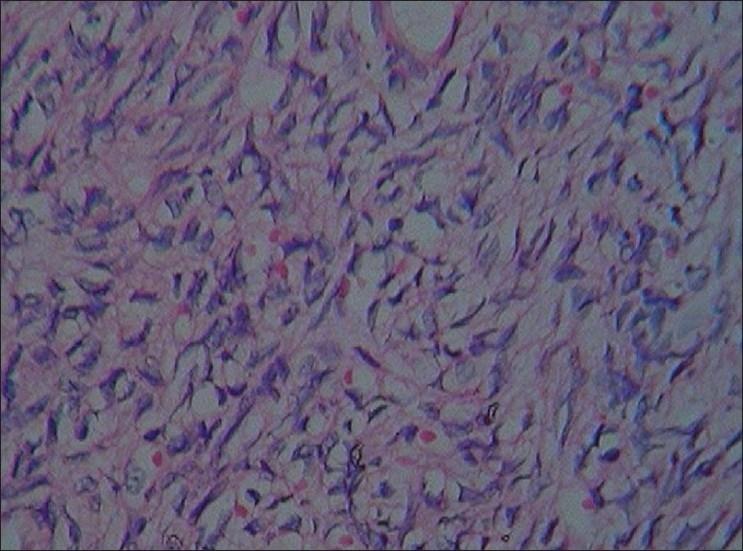

We present a rare case of epithelioid hemangioendothelioma (EHE) in the nasal cavity of a 40-year-old Indian male who presented with history of intermittent epistaxis. The lesion was tested for a panel of immunohistochemical markers like vimentin, CD31, CD34, Factor VIII, vascular endothelial growth factor (VEGF) and Ki67. Immunohistochemically, the neoplasm showed striking positivity for vimentin, CD31, CD34 and weak positivity for VEGF; positivity was also noted for Factor VIII especially in the miniature intracytoplasmic vascular lumina.

我们报告一例罕见的鼻腔上皮样血管内皮瘤(EHE),患者为一名40岁印度男性,有间歇性鼻出血病史。对该病变进行了一组免疫组化标志物检测,如波形蛋白、CD31、CD34、凝血因子VIII、血管内皮生长因子(VEGF)和Ki67。免疫组化结果显示,肿瘤对波形蛋白、CD31、CD34呈显著阳性,对VEGF呈弱阳性;凝血因子VIII也呈阳性,尤其是在微小的胞质内血管腔中。